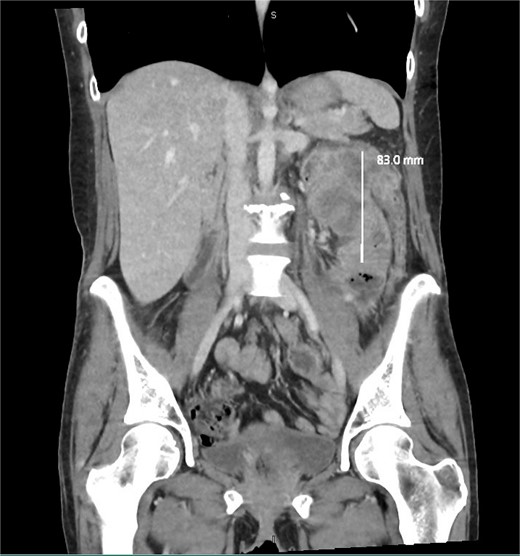

We report a 47-year-old Indigenous woman presenting to a rural centre with nausea, vomiting and abdominal pain. She denied haematochezia or weight loss. Medical history was significant for a previous anterior resection for a T4bN2bM1 (19/44 nodes positive) sigmoid adenocarcinoma ten years prior. The patient received adjuvant chemotherapy with capecitabine at that time, however had poor compliance, did not attend follow up appointments or receive surveillance imaging or colonoscopies. There was no family history of malignancy. There was significant alcohol, tobacco and marijuana use. On examination, she had upper abdominal tenderness without a palpable mass. CEA was 4.6 ug/L, and there was normocytic anaemia. Computed tomography revealed a 7 × 9 × 7cm non-obstructing necrotic splenic flexure mass with adjacent small bowel invasion, however no recurrence at the site of previous anterior resection (Figs 1 and 2). Colonoscopy showed an ulcerated circumferential mass which was unable to be traversed. The patient was transferred to our metropolitan tertiary centre for ongoing management.

Coronal slice of a CT demonstrating necrotic mass arising from the large bowel with significant wall thickening.